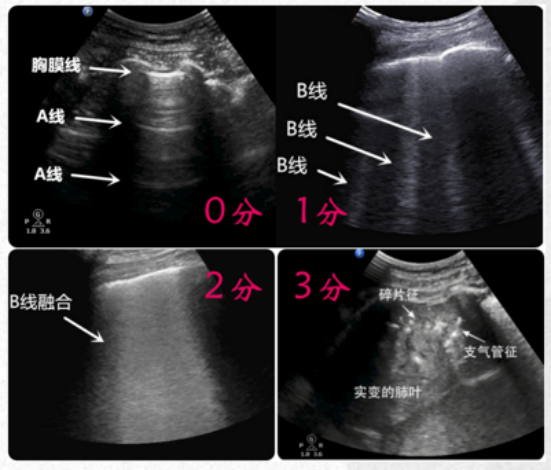

肺部超声有两种方式:一是BLUE方案,根据受检者双手比例进行5个“蓝点”的体表定位,超声快速检查这5个标志性“蓝点”,可以迅速排除和诊断急性呼衰的病因(图1)。二是12分区法,将胸壁划分为12个区域,进行整体区域扫查,精细化筛查病灶,并且进行评分(图2)。

肺通气的超声征象分为四组:①正常模式(N),表现为肺滑动征伴A线或孤立的B线(<3),记0分;②肺通气中度丧失,出现多条B线(>3),记1分;③严重的肺通气损失,显示为融合B线,记2分;④肺组织实变征象记3分。在分析过程中,每一个特定的区域最差的超声波征象为计分标准,并将所有点的得分相加。结果显示,肺部超声评分(LUS)与多个ARDS预后指标[血管外肺水指数(EVLWI),肺损伤评分(lung injury score,LIS),呼吸系统顺应性(Crs),氧合指数]密切相关,能够准确评估ARDS治疗的疗效,如PEEP的设定、肺复张的疗效,并能够预测ARDS患者死亡风险。与其他检查相比,肺部超声是一种无创、经济、可重复、简单的床旁检查方法,但肺气肿、肥胖、导管敷料等都影响超声的评定,测量参数有一定的主观性。弥漫性肺泡损伤(DAD)是ARDS的病理标志。一项研究分析了是否可以使用高分辨率CT(HRCT)评分来预测与DAD相关的60 d死亡率,研究共纳入34例在ARDS诊断后7 d内接受HRCT的DAD患者,并被分为60 d存活组和未存活组,每组17例患者。采用Ichikado等提出的HRCT评估急性间质性肺炎评分系统评估ARDS,HRCT表现根据分级系统按1~6分进行评分,1分为正常衰减,2分为磨玻璃影,3分为实变,4分为磨玻璃影伴牵引性支气管扩张或细支气管扩张,5分为实变伴牵引性支气管扩张或细支气管扩张,6分为蜂窝状。单因素和多因素二元回归分析以及ROC曲线显示,牵引性支气管扩张或细支气管扩张的总面积百分比是60 d死亡率的独立预测因子,具有良好的预测性能。存活患者的HRCT表现为广泛的磨玻璃影和实变,支气管壁光滑(图4B)。未存活患者的HRCT表现为双侧磨玻璃影、网状和明显的牵引性支气管扩张(图4D红色箭头)。图源:J Clin Med, 2022, 11(9):2458.肺部炎症是ARDS的关键特征之一。氟代脱氧葡萄糖(FDG)是一种具有生化活性的葡萄糖抗代谢产物,FDG被组织细胞吸收后可在PET-CT扫描显像。中性粒细胞活化在代谢上的特征是每个细胞的葡萄糖利用率增加,从而增加FDG摄取。在急性肺损伤(ALI)期间,FDG PET可用于监测肺中性粒细胞活化情况。同时,在ALI状态下,巨噬细胞对FDG信号的变化较小,淋巴细胞在体外激活后FDG摄取增加。内皮细胞活化后具有高度代谢活性,摄取FDG增强,肺泡上皮细胞受损后也可以促进FDG的摄取。因此,FDG PET可能是一种有价值的非侵入性方法,可用于全面了解ALI/ARDS的发病机制,早期预测ARDS的发生和评估预后。研究发现,单侧吸入烟雾导致急性损伤的单侧绵羊肺中区域FDG摄取显著增加(图5,图6)。在该模型中,区域FDG标记葡萄糖摄取可以预测区域气体交换损伤,表明存在功能-炎症关系。研究结果还表明,损伤前的通气-灌注异质性程度与损伤后FDG摄取的程度之间存在直接关联。